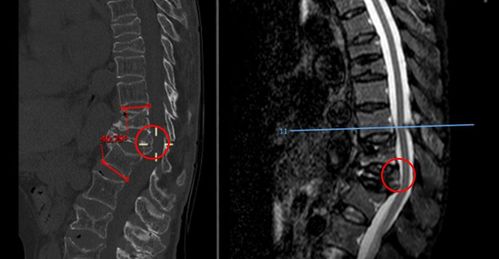

二骨二区,41床.张穗英,女,69岁,t12椎体压缩性骨折

t12椎体压缩明显,椎体后缘 向后突出占位,压迫脊髓

ct示:t12椎体压缩性粉碎性骨折并骨性椎管狭窄严重.

t12椎体压缩性骨折(田欢)